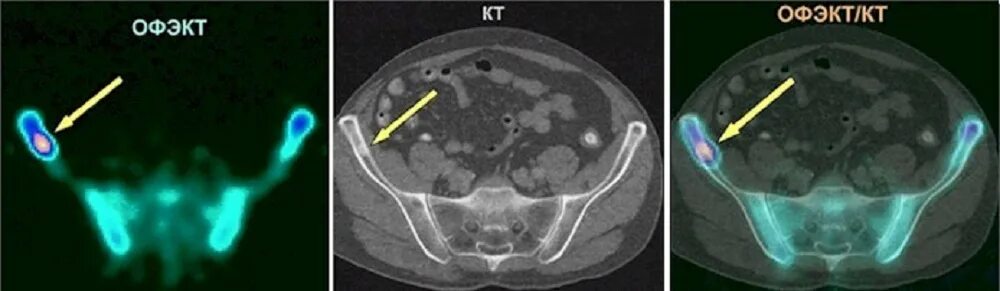

Пт кт